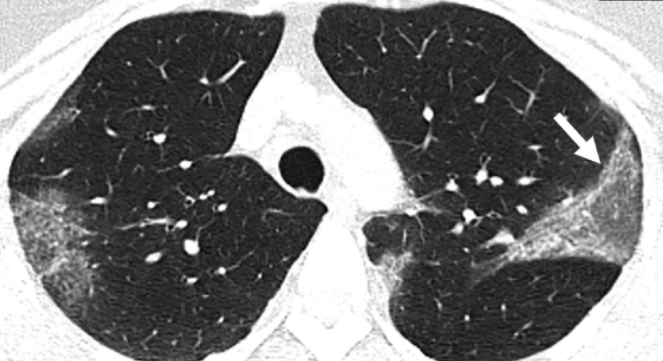

هاوڵاتى سهرپهرشتیاری تیمی روبهڕوبونهوهی كۆرۆنا له سلێمانی و پسپۆڕ لهبواری ههناوی، جیاوازیهكانی سیهكانی نێوان ئهو كهسانهی خستهڕو كه ڤاكسینی كۆرۆنایان وهرگرتوه لهگهڵ كهسانێك كه ڤاكسینهكهیان وهرنهگرتوه و رایگهیاند، ئهگهر ڤاكسین رێگری لهتوشبونیشت بهكۆرۆنا نهكات، ڕێگره لهوهی بهسهختی توش ببیت. دكتۆر ھێرش حهیدهر سهرپهرشتیاری تیمی روبهڕوبونهوهی كۆرۆنا له سلێمانی و پسپۆڕی ههناوی، لهههژماری تایبهتی خۆی تۆڕی كۆمهڵایهتی فهیسبوك، جیاوازی سیهكانی كهسێك كه ڤاكسینی كۆرۆنای وهرگرتبێـ لهگهڵ كهسێك كه وهرنهگرتبێت بڵاوكردوهتهوه و نوسیویهتی، "سهرنجتان ڕادهكێشم بۆ ئهم دو وێنهیهی خوارهوه كه بهڕونی جیاوازی سیهكانی كهسێك كه ڤاكسینی وهرگرتبێت و كهسێك ڤاكسینهكهی وهرنهگرتبێت دهردهخات". ئهوهشی خستهڕو، "ههردوكیان ئهگهری توشبونیان بهكۆرۆنا ههیه، بهڵام جیاوازیهكهی لهوهدایه ئهو كهسهی كه ڤاكسینهكهی وهرگرتوه ڕێژهكهی زۆر كهمتره و بهئاسانی ڤایرۆسهكهی تێپهڕاندوه وهك لهوێنهكهدا دیاره، بهڵام ئهوهی كه ڤاكسینهكهی وهرنهگرتوه باری تهندروستی ناجێگیره و لهنهخۆشخانهیه". دكتۆر ھێرش حهیدهر باسی لهوهشكرد، "ڤاكسینی كۆرۆنا ئهگهر ڕێگریش نهكات له توشبونت بهكۆرۆنا، كه تا ڕادهیهكی باشیش ڕێگره، بهڵام ڕێگره لهوهی بهسهختی توش ببیت و سیهكانت وێران بكات".